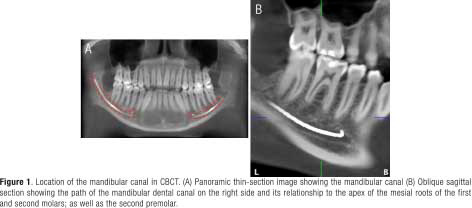

The lower occlusal plane was leveled to the floor in the cross-section, and the panoramic reformation was performed using the “Manual panoramic” tool. Points were then placed following the path of the mandibular canal using the “Draw Nerve” tool. The position of the mandibular canal and the apices was assessed in the oblique sagittal view, with an interval of 1mm (Figure 1). The vertical distance from the upper edge of this canal (POINT A) to the apex of the mesial roots of the first molars and second molars (POINT B) was measured in oblique sagittal sections, as well as the distance from the roots of the second premolars that presented a single root in the right and left hemiarch in men and women, using Planmeca Romexis®5.3.3.3 software (Figure 2) (21). The data were entered into a data collection form, where each tomography measurement was recorded by means of codes, with the following recorded: sex, age, hemiarch, and the vertical distance of each root apex of the first molars, second molars, and second premolars. Planmeca Romexis® 5.3.3.5 software and iMac MXWT2LL/A (Apple brand with an Intel Core i5-6700K processor with 8 GB of RAM memory and 256 GB of SSD) were used to perform the respective measurements.